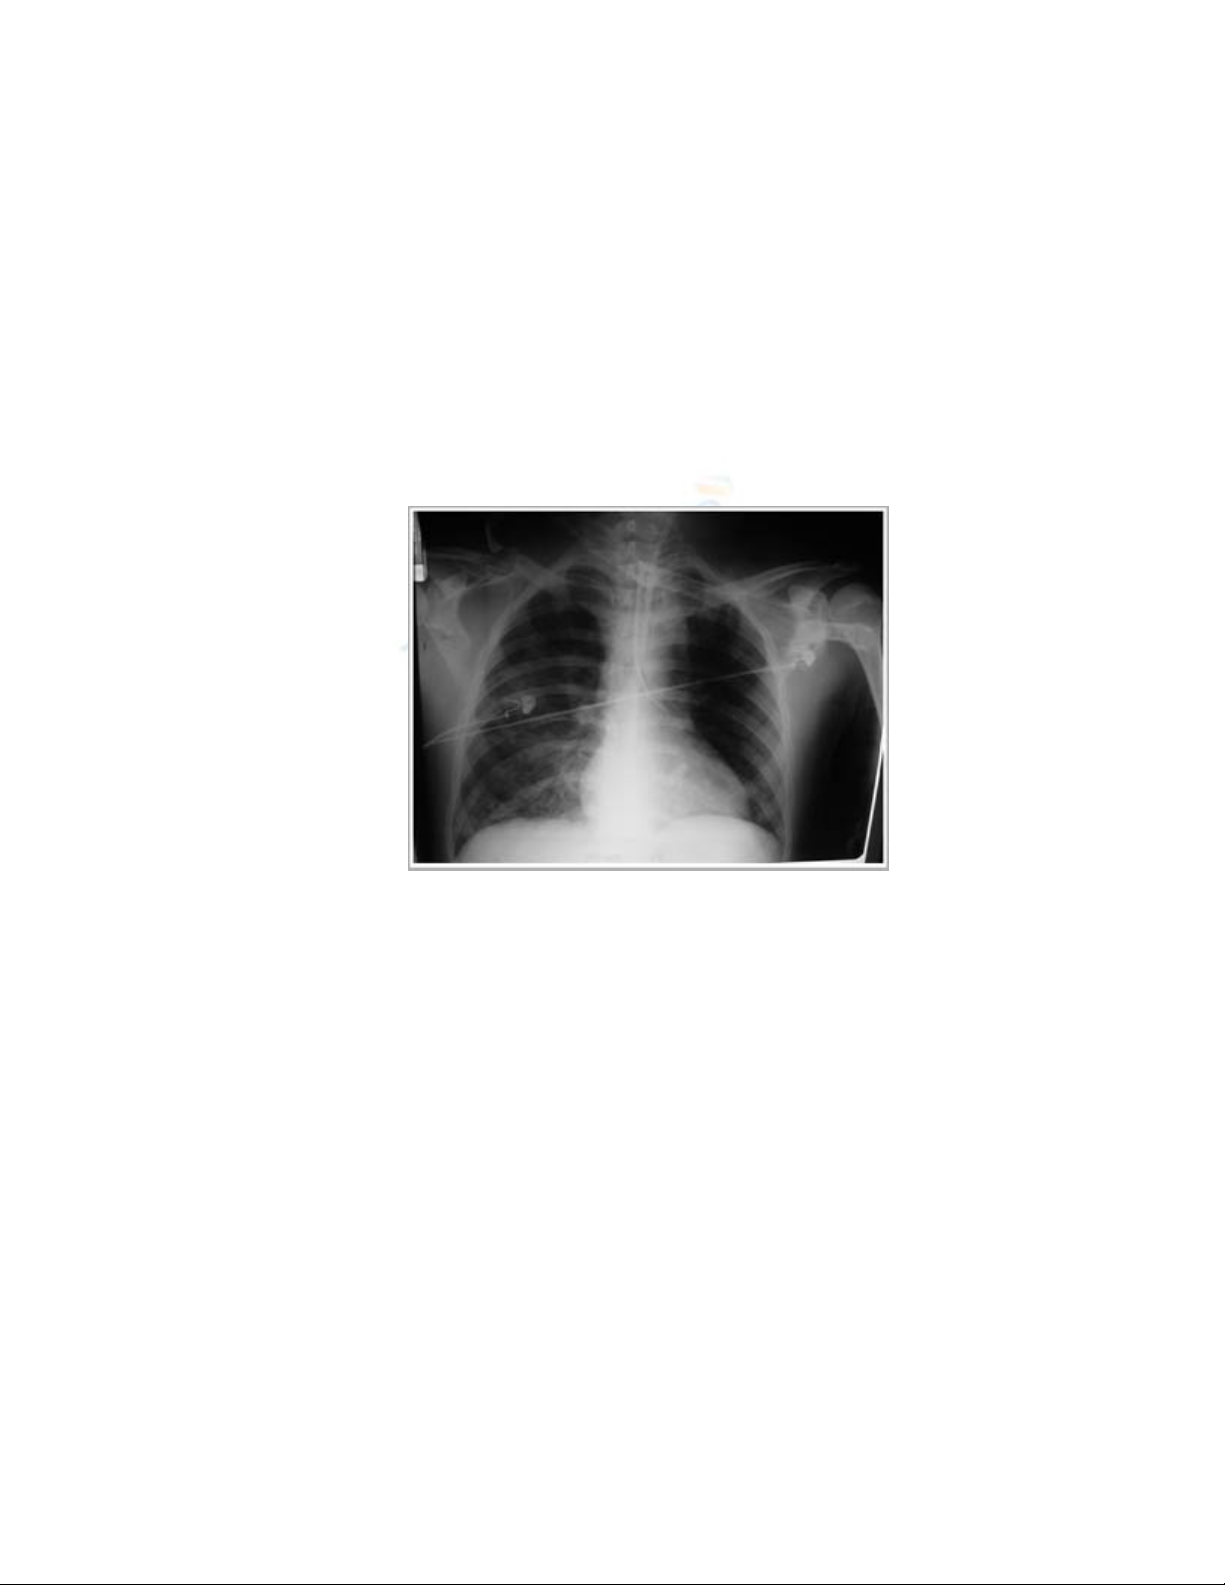

c. Phim lồng ngực:

Xét nghiệm này cần thực hiện để có thể phát hiện những tổn thương ở chủ

mô phổi, màng phổi, trung thất.